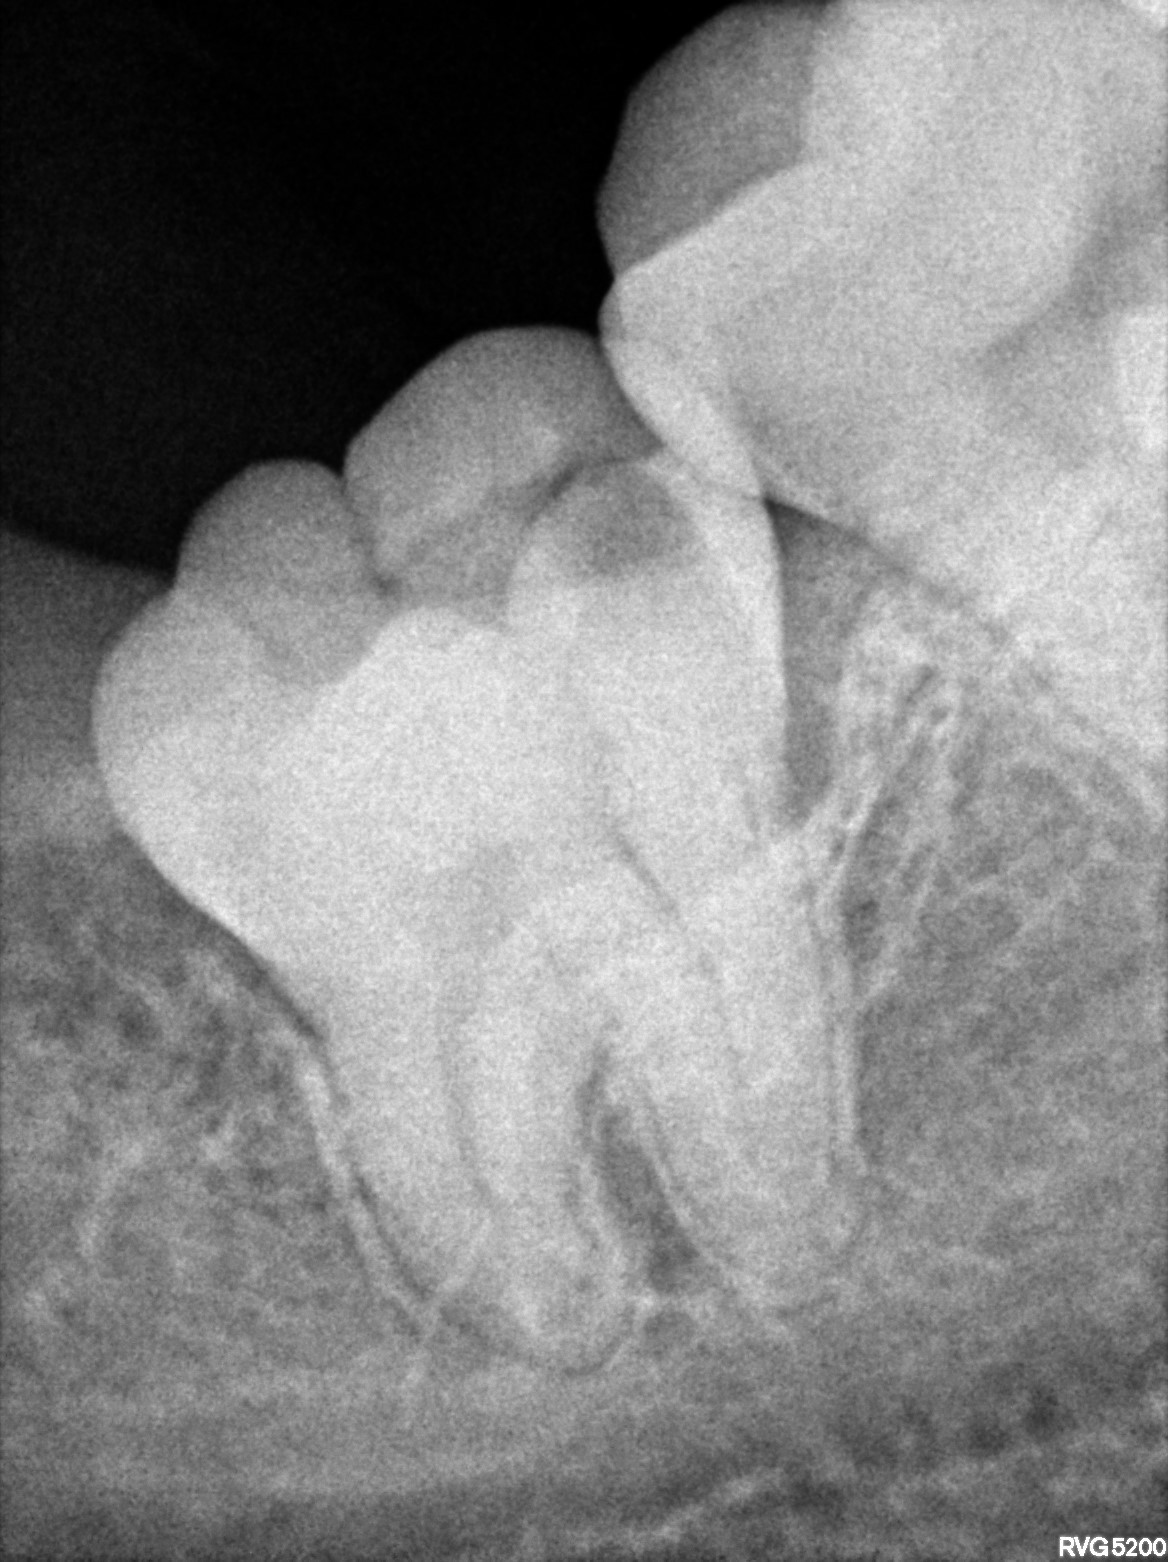

Dental Radiographs FHIR: DocumentReference · LOINC 24641-7

xray_1772642539_0.jpg

24641-7